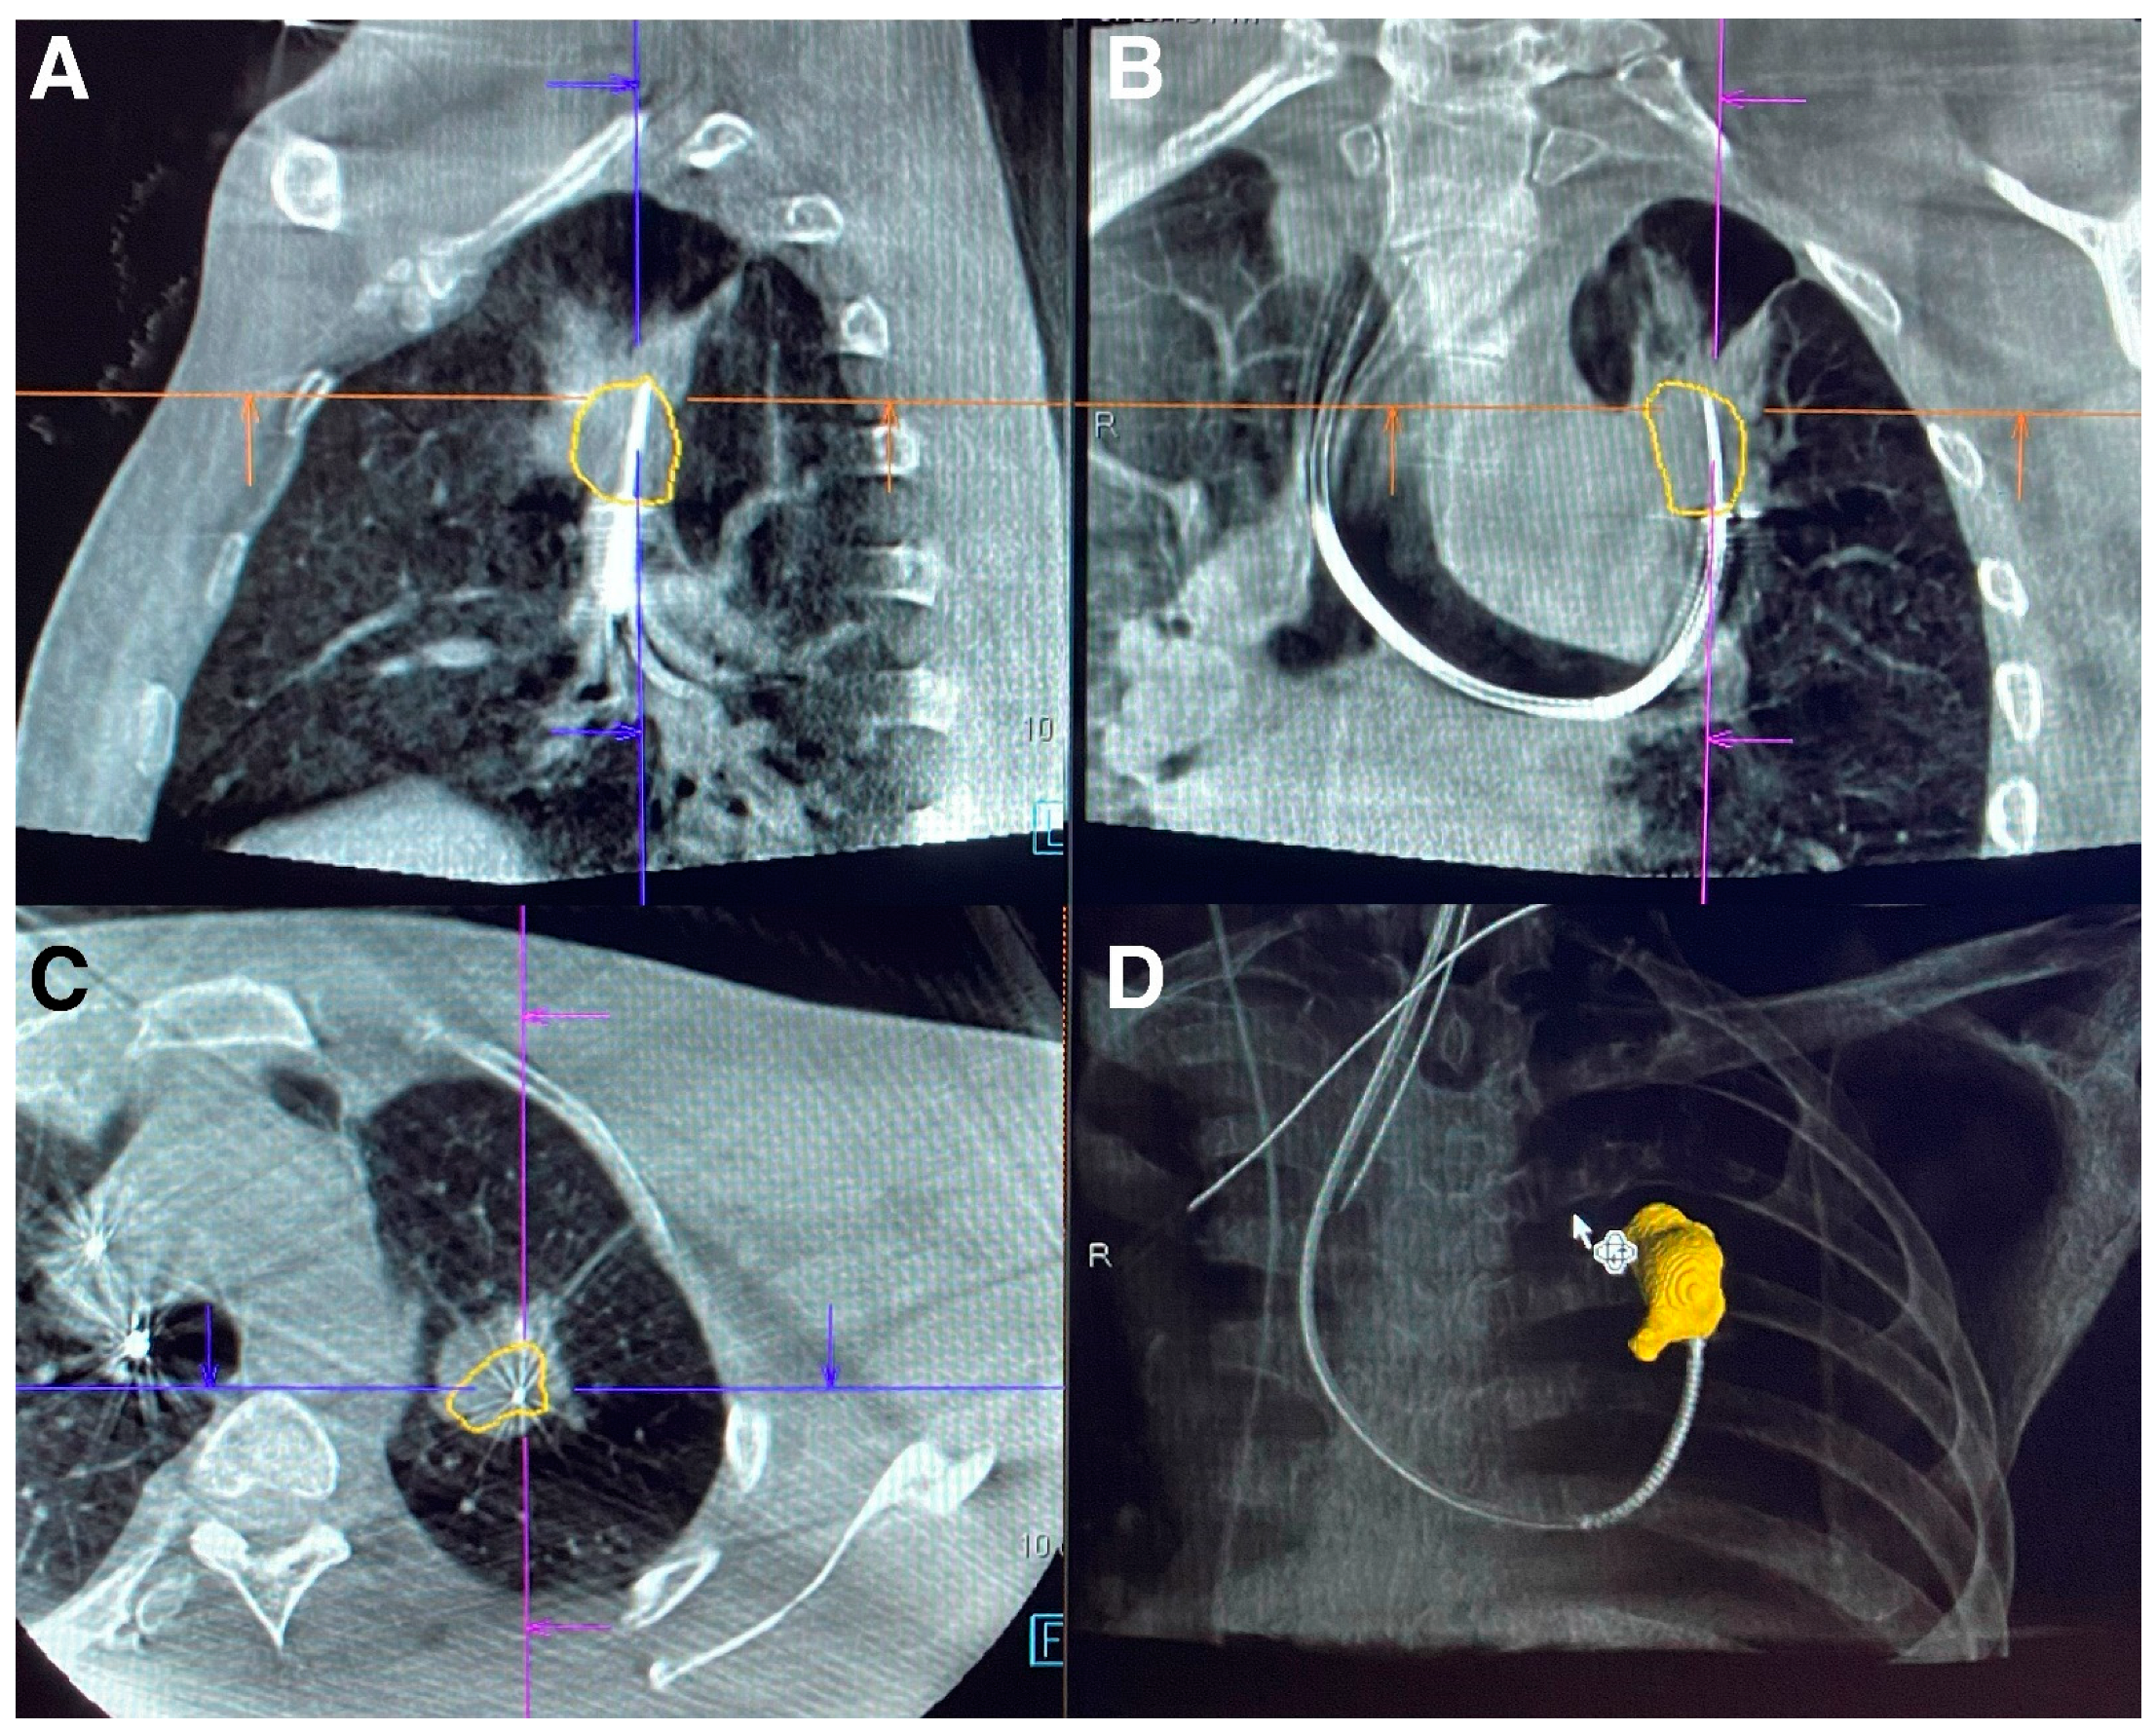

- Kalchiem-Dekel, O.; Fuentes, P.; Bott, M.J.; Beattie, J.A.; Lee, R.P.; Chawla, M.; Husta, B.C. Multiplanar 3D fluoroscopy redefines tool-lesion relationship during robotic-assisted bronchoscopy. Respirology 2021, 26, 120–123. [Google Scholar] [CrossRef]

- Reisenauer, J.; Duke, J.D.; Kern, R.; Fernandez-Bussy, S.; Edell, E. Combining Shape-Sensing Robotic Bronchoscopy with Mobile Three-Dimensional Imaging to Verify Tool-in-Lesion and Overcome Divergence: A Pilot Study. Mayo Clin. Proc. Innov. Qual. Outcomes 2022, 6, 177–185. [Google Scholar] [CrossRef]